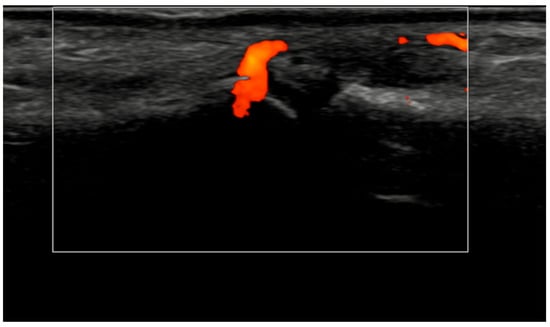

Figure 4.

Longitudinal ultrasound image of the PIP III joint showing synovial hypertrophy (grade 2) and intra-articular power Doppler signal with distal capsular and entheseal extension (PD grade 2), corresponding to a combined EULAR–OMERACT synovitis grade = 2 (joint level).